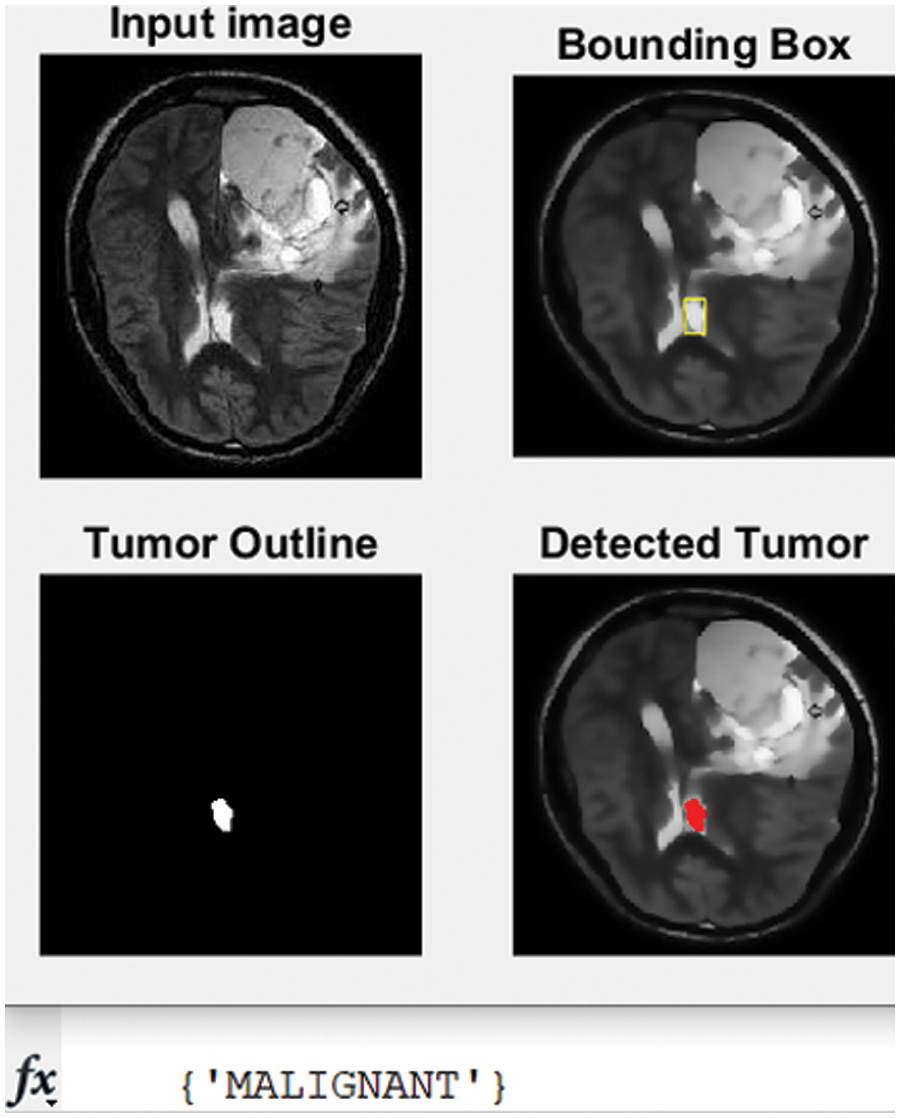

MATLAB is used in this research to conduct numerous experiments on a machine that runs Windows 11 Pro. The specifications are an Intel Chip of Core i7 of 8th generation, the clock speed is 2 GHz, and the RAM size is 16 GB. The dataset from the Kaggle website contains 3865 images of patients diagnosed with a brain tumor or no tumor. These MRIs were utilized to verify the precision, accuracy, recall, and correctness of the presented method in this research. Figs. 7–9 illustrate the obtained results for different MRIs. Each figure contains four subgraphs in which (A) is an input image in the upper lefthand corner, (B) is the detected potential area (tumor) bounded by the yellow rectangular box in the upper right corner, (C) is the detected tumor outline in the bottom left corner and (D) in the bottom right corner shows the detected tumor in red. The performance evaluation is detailed in two forms, which are quantitative and qualitative, of the obtained accuracy, precision, and recall. These three metrics are considered the most critical factors, and several studies use them to measure the developed algorithms. The presented system has evaluated the whole dataset. In the final phase, the proposed system receives inputs from both classifiers, as depicted in Fig. 4. The computed performance metrics are evaluated for the whole dataset, and the average value is taken for every metric. This section mainly focuses on evaluating the required factors and assessing them against implemented systems of the literature review. The dataset contains different sizes, which are resized to speed up the processing time. Figs. 7–9 provide a brief detection and classification results analysis when applying ten distinct runs. These three figures indicate that the proposed system has proficiently identified and classified the images under different runs. For instance, the system reached 92.3%, 93.51%, and 92.87% for accuracy, precision, and recall, respectively, in the first distinct run, and these figures increased as the number of distinct runs increased. The maximum obtained accuracy was 99.47% which is higher than measured. Fig. 10 illustrates the chart of the obtained values of the considered three performance metrics for ten distinct runs. One represents accuracy, two refers to precision, and three represents recall in the same figure. This graph shows that the accuracy increases after each distinct run while the precision and the rise in recall slightly reach an acceptable level of over 99%.

Figure 8: The second tested MRI and the detected tumor with its classification

Figure 9: Original MRI, the detected, and classified tumor

The developed algorithm also outlines tumors to justify and validate the correctness of the presented method. The detected tumor in Fig. 7 was slow-growth, while Figs. 8 and 9 show that the algorithm detected an aggressive or malignant tumor. In the previous three figures, Figs. 7–9, the proposed algorithm identified the tumors and classified them correctly.